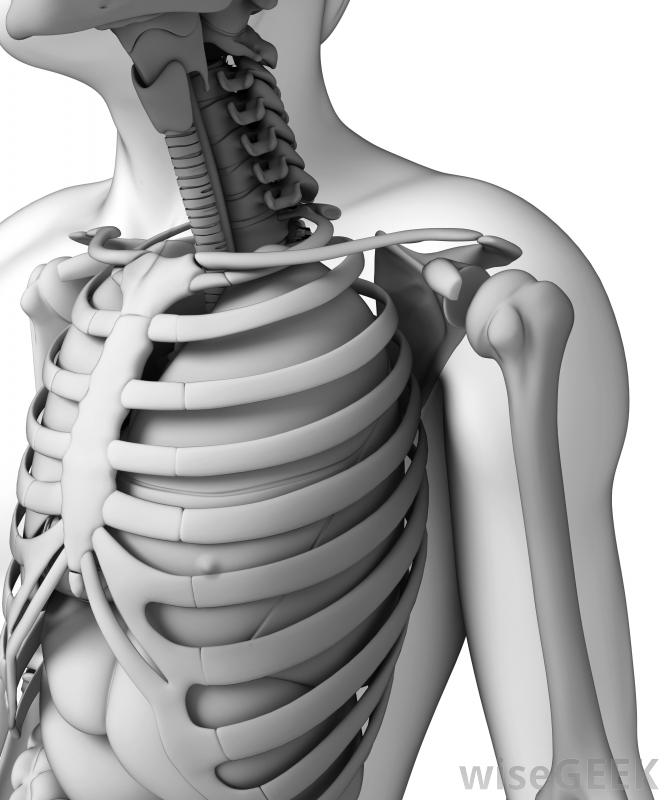

胸廓也被稱為胸腔。它由12對肋骨組成,通過12根椎骨連接到身體后部,胸椎是脊椎的一部分,位于頸椎或頸部的正下方。保護心臟、肺等重要器官,肝臟和胃是胸腔的一個非常重要的功能上部10對肋骨連接在身體前部,或前部。由于上部的7對肋骨圍繞側面朝前彎曲,每根肋骨都會遇到一塊薄薄的軟骨,這是一種非常堅韌但柔韌的組織。軟骨延伸到它與胸骨相連的地方,通常稱為胸骨胸腔包括12對肋骨,胸骨和12個椎骨。第八、第九和第十對也環繞在身體前部,但是連接到胸骨的軟骨是共享的,而不是單獨的一塊,第11對和第12對肋骨沒有前部附著物,這就是它們通常被稱為"浮動"肋骨的原因胸前胸腔的插圖和X光片可能只顯示第11對肋骨的一部分,而第12對肋骨往往很短,除了從身體的側面或背面看,它根本看不出來。手術時有時需要切開胸骨才能進入胸腔。肋骨與胸骨相連的肋軟骨阻止了整個胸腔的形成骨骼。這一點很重要,因為呼吸依賴于胸腔的擴張和收縮,而骨骼太硬,無法滿足胸腔內呼吸所需的靈活性。胸腔的形狀被稱為籠子,因為它包圍了身體的大部分軀干和肋骨對制作類似于籠子的鋼筋外觀。第12對肋骨可能在X光片上看不到外行人士不應期望能夠觸碰到漂浮的肋骨對或構成胸腔一部分的肋軟骨。肋骨任何部分的骨折都可能導致極度不適和胸腔器官損傷例如,汽車事故可能會導致一個人的胸部突然受到方向盤的強力擠壓,導致一根或多根肋骨骨折,可能刺傷心臟、肺、肝臟或胃,導致內出血可能進行胸部影像學檢查以診斷胸部損傷,除了休息、冰和非甾體抗炎藥之外,很少有治療方法可用。在心肺復蘇過程中實施胸部按壓可能會導致肋骨骨折。